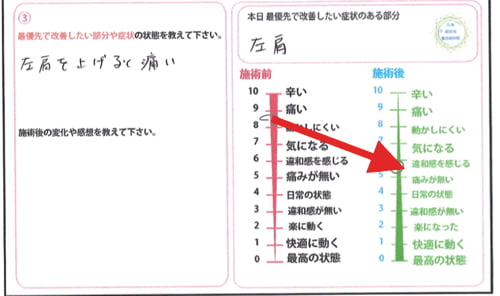

施術前後のアンケート

痛くて上がらなかった腕が、違和感は残るものの痛み無く挙げられるようになりました。